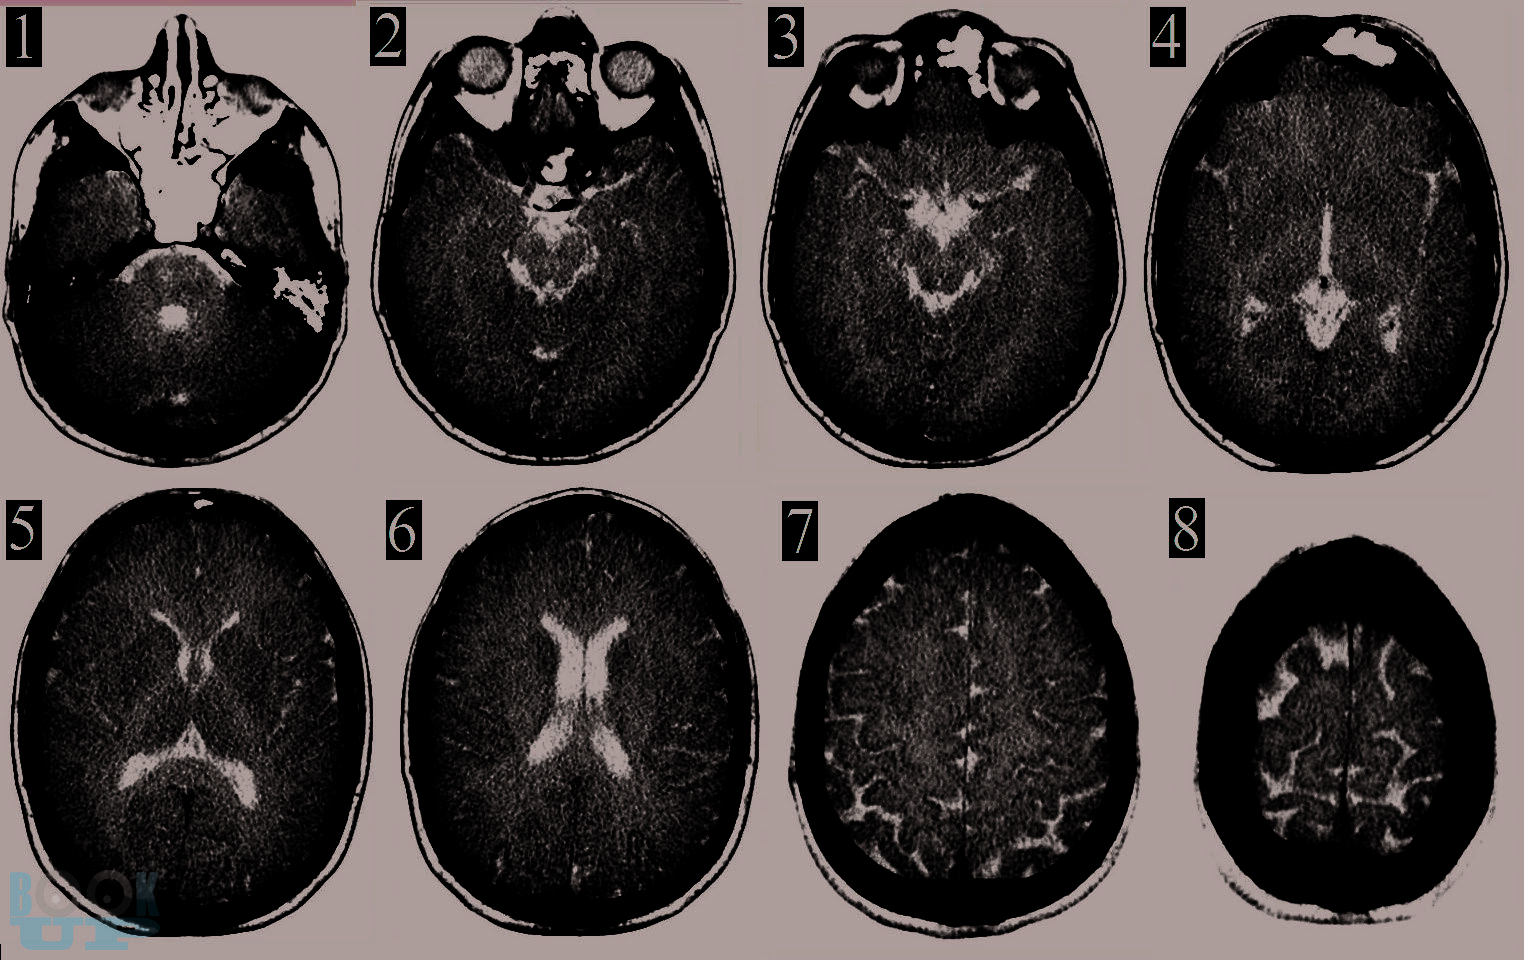

В этой книге мы рассказываем о динамике и взаимосвязи патологических процессов. Эти знания позволяют обосновать вашу тактику. В книге обсуждаются взаимосвязь первичного и вторичного повреждения мозга. Как внутричерепная гипертензия приводит к дислокациям и вклинениям головного мозга и/или нарушениям кровоснабжения мозга. Обсуждается регуляция тонуса сосудов мозга в норме и патологии. Зависимость церебрального перфузионного давления от среднего артериального давления, внутричерепного давления и сохранности ауторегуляции тонуса мозговых сосудов. Рассматриваем варианты отека мозга и возможности лечения. Мы рассказываем как на основе результатов мониторинга внутричерепного давления принимаются решения о том как лечить пациента.